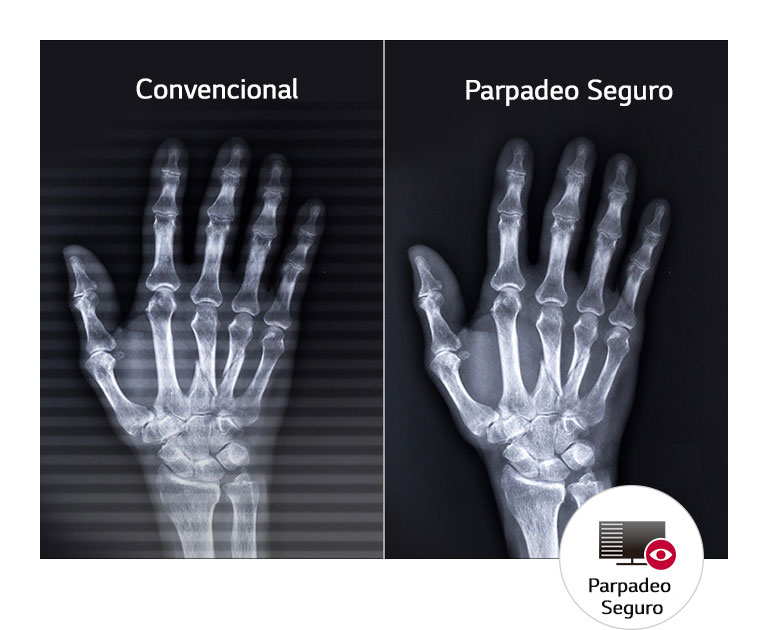

Comodidad de Vista Mejorada

A prueba de parpadeos

SIM